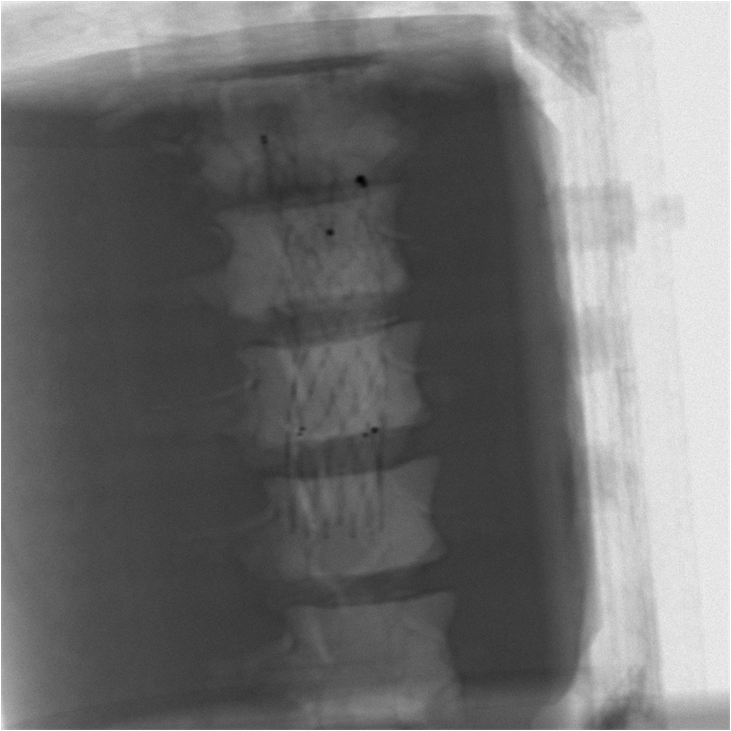

3.4 Phantom experiments

A phantom targeting experiment was conducted to evaluate the accuracy of needle insertion. Fig. 9A shows the experimental setup, including an endoleak phantom, an FG mounting frame, and a Canon Alphenix C-arm (Canon Inc., Tokyo, Japan). Three magnetically tracked needles were inserted into the endoleak phantom. During 2D navigation, the tracked needles (red lines) were projected on the fluoroscopic image, while the actual needles appeared as dark lines. The discrepancies between the two were used to quantify 2D targeting accuracy.

Fig. 9B illustrates the 3D navigation, including 3D reformations, the rendered contrast-enhanced CT volume, and tracked needles. To validate 3D needle insertion accuracy, we acquired a post-insertion non-contrast CT image (Fig. 9C). The inserted needles were clearly visible in three orthogonal views, with the 3D view displaying the inserted needles in silver and the tracked needles in cyan. Needle tip and angle errors were calculated by comparing the tracked needles with their segmented counterparts from the CT image. This process was repeated three times, with a total of nine inserted needles. The overall needle insertion errors were for the tip, and for orientation, as shown in Table 5.